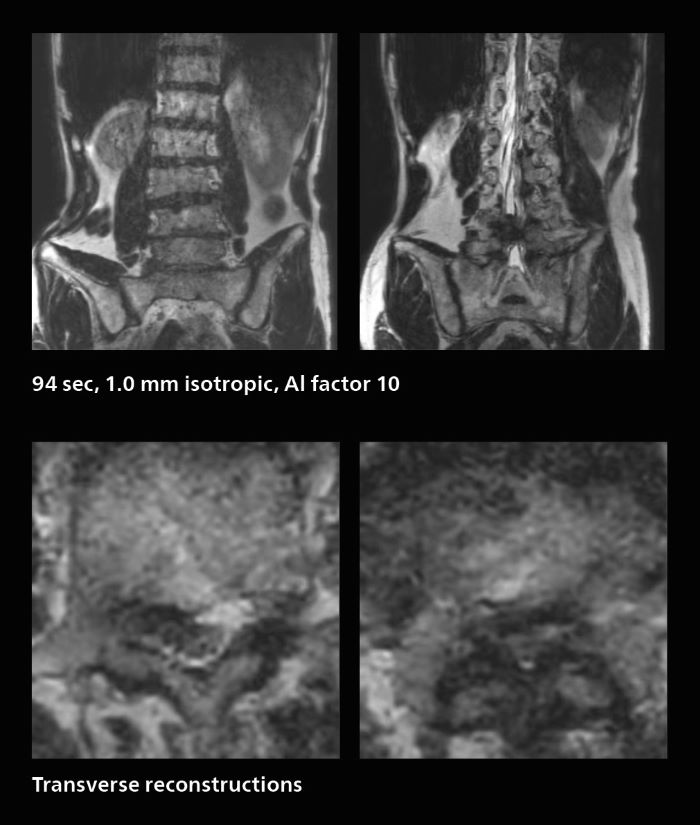

Many patients who must undergo a lumbar spine examination suffer from back pain. For these patients it is difficult to maintain the imaging position long enough to successfully complete the examination. “In such cases, using SmartSpeed allows us to perform volume imaging, so that we acquire only one high resolution 3D sequence in a short time and then reconstruct the other orientations from that,” Dr. Katahira says. “This is highly advantageous because the patient needs only endure a short exam time, whereas before it was necessary to acquire a larger number of sequences in total. We have seen that the shorter time has allowed us to scan patients who previously could not finish the exam. This is a great advantage.”

A patient arrived saying that undergoing MRI was not possible because of severe back pain and leg pain, was imaged with SmartSpeed in only 94 seconds. The scan was diagnostic and afterwards the patient confirmed that it only took a little while. Performed on Elition X.

The hospital’s fast lumbar spine ExamCard includes T2W SpineVIEW, 1:40 min, 1.0 mm isotropic, acceleration factor 12.

In this patient MRI was done to help in diagnosing the depth of invasion. Performed on Elition X.